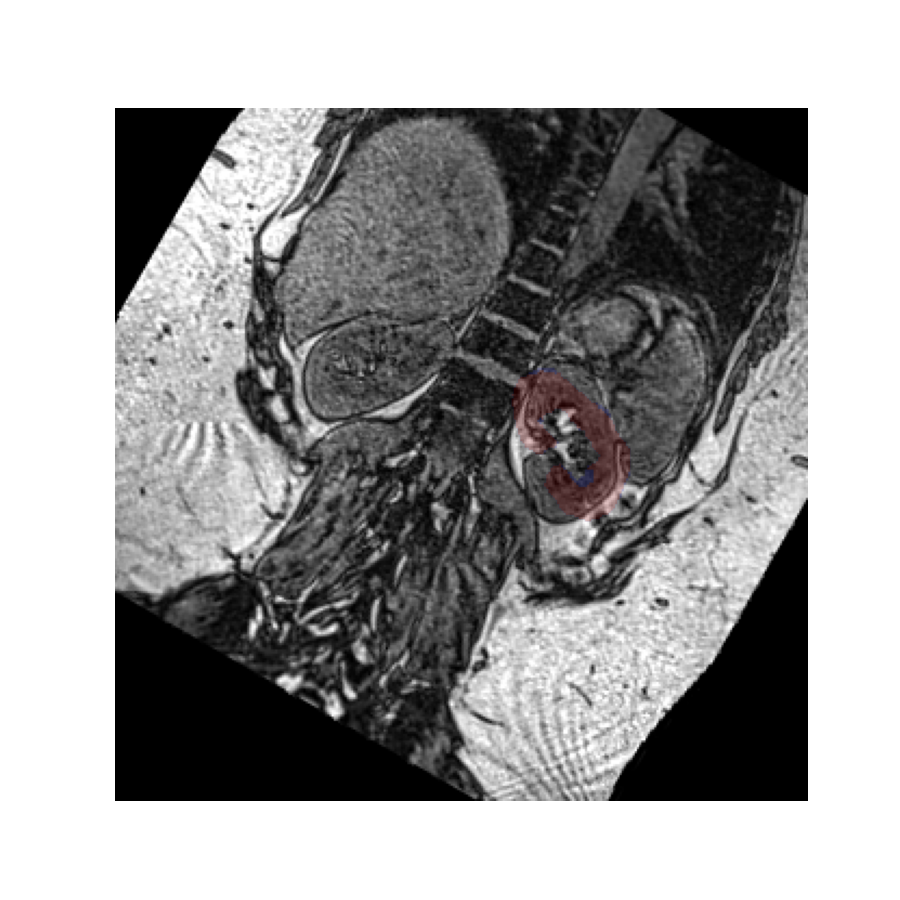

Let’s perform the above rotation again, but now passively using it only to reslice the values. We use the oppositive sign of the rotation vector to get a comparable result as before:

The rotated image looks exactly the same as in the previous example, but in this case the kidney mask is still in the same place. This is because the volume has not actually been rotated in space - it has merely been resliced at an angle so we see it in a different plane.